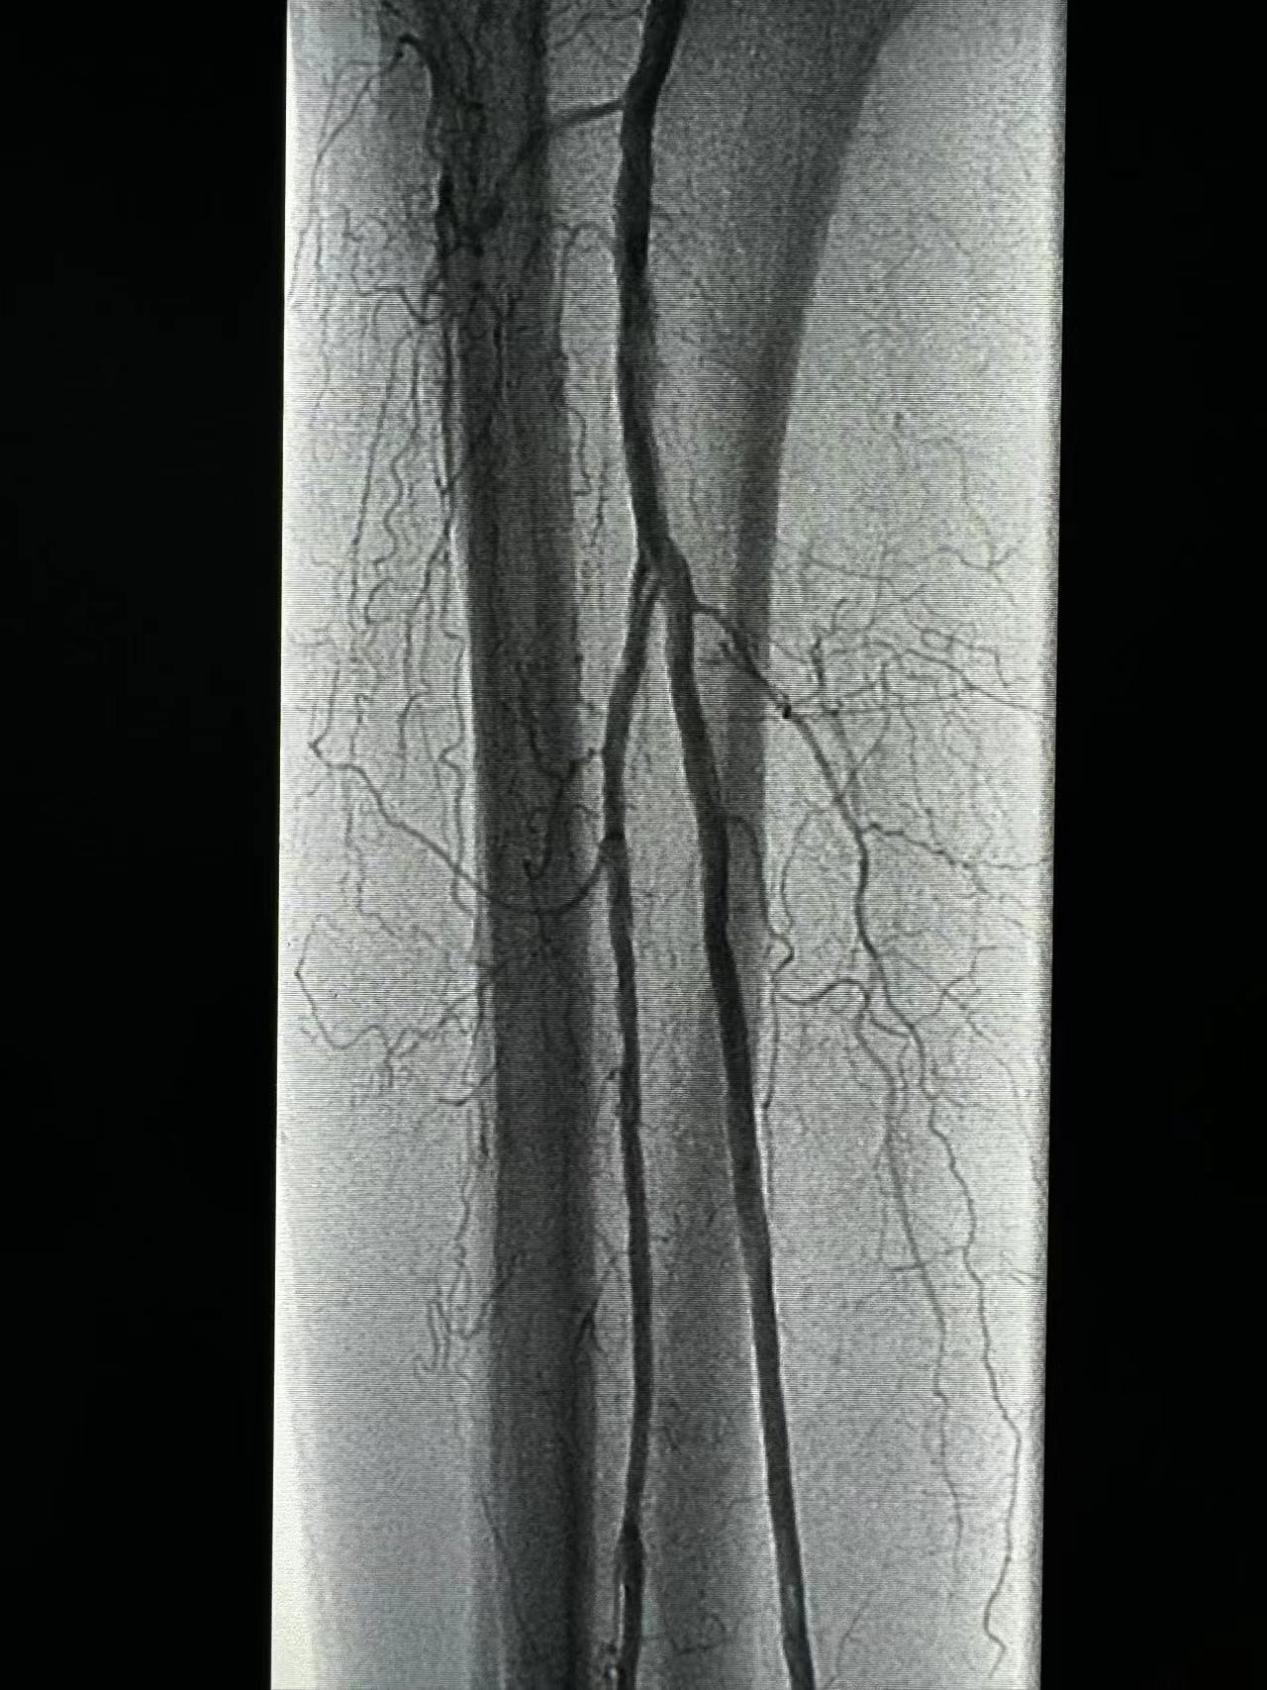

患者男,70歲,右下肢跛行3月余,右足趾壞疽1月。診斷:下肢動脈硬化閉塞癥術(shù)前造影股淺中段多處重度狹窄,收肌管段閉塞,腘動脈多處重度狹窄,脛腓干動脈閉塞,脛后近段、腓動脈近段重度狹窄。?